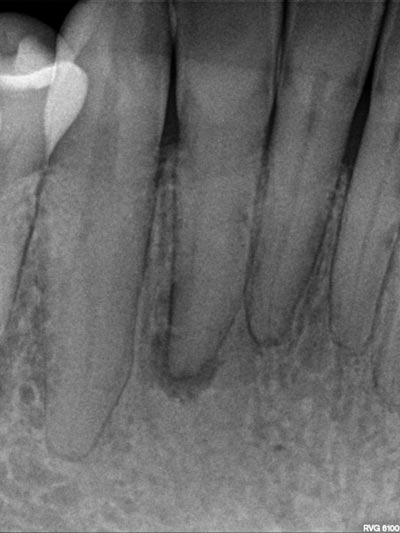

Imágenes: Endodoncia en un incisivo inferior calcificado y necrótico.